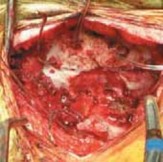

1. An oblique incision overlying the posterior rib allows for adequate exposure.3

1. The muscle fibers are separated and dissection is carried down to the periosteum of the rib.

2. Adequate rib is exposed and cut.

1. The size of the rib graft is greater than the area to be fused because part of the rib is used as morcelized graft.

2. Using a rib cutter, the graft is cut distally and proximally and removed (

TECH FIG 2A

).

3. Irrigation fluid is placed in the surgical site and positive pressure applied to check for pleural leaks.

4. If a pleural tear is detected, air can be removed from the chest cavity by using a red rubber tube and suction.

5. A larger leak may require placement of a thoracostomy drainage tube.

1. In all patients, a chest radiograph should be taken after rib harvest to rule out pneumothorax.

6. Two full-thickness structural grafts are prepared to fit the arthrodesis site.

7. The rib grafts can span large defects and fit nicely into large or abnormally shaped skull, and we find this best for young infants.

8. 16- or 18-gauge wire is looped through the burr holes on each side of the midline (see TECH FIG 1C).

1. The burr holes are drilled and aligned similarly to the ones described for the iliac graft technique.

1. There is no need to create a groove at the base of the occiput.

54. Braided cable or no. 5 Mersilene sutures may be used instead of wire.

1. With Mersilene sutures there is a reduced risk of cutting out in thin bone of poor quality.

55. After this, purchase of two wires is made to the posterior elements of most caudal vertebra on each side of the midline by sublaminar wiring.

56. Suitable grafts on either side are then secured to the occiput and lamina of the most caudal vertebra by wires.

1. The stability of the grafts is checked under radiographic control and the wires are then crimped and cut (

TECH FIG 2B,C

57. Adjustments are made by flexion–extension of the halo frame, contouring of the graft, and appropriate tightening of the wire.

1. Intraoperative radiographs are obtained to confirm acceptable reduction, alignment, and placement of the graft.

58. For both techniques, morcellized autograft is packed into the arthrodesis site. The wound is closed in layers.

59. The halo vest is worn for 8 to 12 weeks after both techniques to maintain postoperative stability (

TECH FIG 2D,E